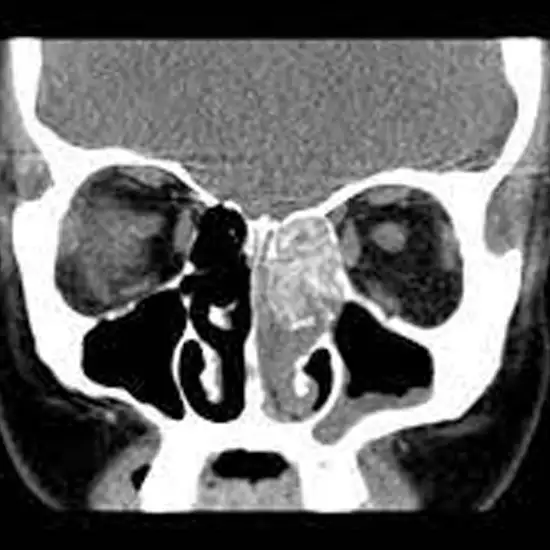

NCCT Nose (Non-contrast computed Tomography of the Nose) is a diagnostic methodology that creates a fully detailed image of the internal structure of the nose. It helps in finding out the major problems associated with bone, soft tissues, and blood vessels of the nose even slight changes. Doctors consider it the best methodology for simple abnormalities as well as chronic conditions in the nose such as a tumour, internal injury as well as internal bleeding.